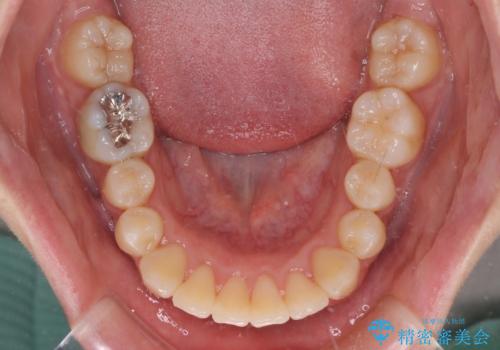

短期間で終了 デコボコをワイヤー矯正で解消

- 上下のデコボコと前歯のクロスバイトを改善したいとのことで来院された患者様です。

極力短期間で治療したいとのことで、ワイヤー装置による矯正治療を行うこととしました。